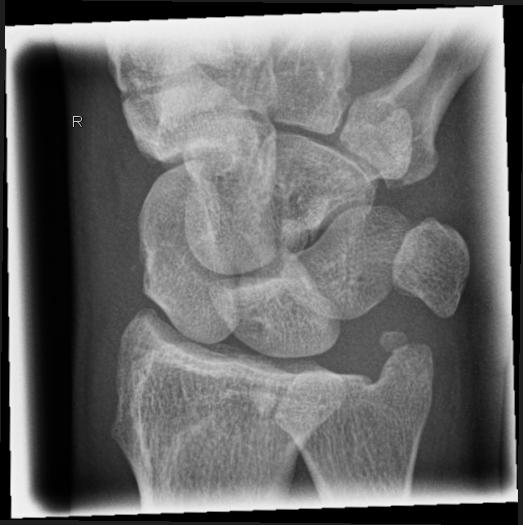

Handgelenk seitlich (radio-ulnar, 2. Ebene)

Technik

• FDA: 1,05 m

• Ausgangsformat: 18/24

• Übertischaufnahme

Indikation

Fraktur

Lagerung

sitzend - seitlich zum Tisch

Handgelenk, Unterarm und abgewinkelter Ellenbogen liegen streng seitlich auf. (Radius und Ulna deckungsgleich)

Zentralstrahl

senkrecht

Querzentrierung auf Gelenkspalt

Längszentrierung auf Objektmitte

Einblendung

distal einschließlich Fingergrundgelenke

Anmerkung

Ulnar und Radius müssen distal übereinander projiziert werden. Os Scaphoideum und Os Lunatum liegen übereinander, ebenso die Mittelhandknochen, bei Verdacht auf Subluxation des Os Lunatums, Zusatzaufnahme in Flextion und Reflextion der Hand notwendig (Stressaufnahme).

ggf. Tisch herunterfahren

Qualitätskriterien

Radius und Ulnar müssen deckungsgleich sein; Mittelhand, Handwurzelknochen und distaler Unterarm sollen abgebildet werden.